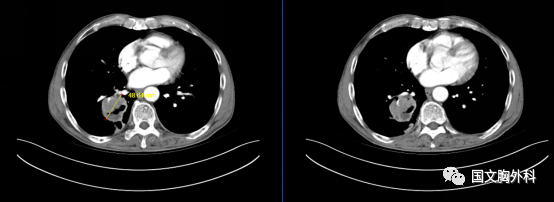

入院時(shí)胸部CT,提示:胸部CT平掃+增強(qiáng):右肺下葉占位,符合肺癌表現(xiàn),伴周圍阻塞性肺炎??v隔、右肺門稍大淋巴結(jié),轉(zhuǎn)移不除外。

治療前 ↓